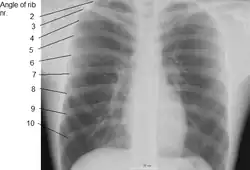

Human ribs are flat bones that form part of the rib cage to help protect internal organs. Humans usually have 24 ribs, in 12 pairs.[2] 1 in 500 people have an extra rib known as a cervical rib. People may have a cervical rib on the right, left or both sides.[3] All are attached at the back to the thoracic vertebrae and are numbered from 1 to 12 according to the vertebrae to which they attach. The first rib is attached to thoracic vertebra 1 (T1). At the front of the body, most of the ribs are joined by costal cartilage to the sternum. Ribs connect to vertebrae at the costovertebral joints.[4]

Rib cage

The first seven sets of ribs, known as "true ribs", are attached to the sternum by the costal cartilages. The first rib is unique and easier to distinguish than other ribs. It is a short, flat, C-shaped bone, and attaches to the manubrium.[6] The vertebral attachment can be found just below the neck at the first thoracic vertebra, and the majority of this bone can be found above the level of the clavicle. Ribs 2 through 7 then become longer and less curved as they progress downwards.[7] The following five sets are known as "false ribs", three of these sharing a common cartilaginous connection to the sternum, while the last two (eleventh and twelfth ribs) are termed floating ribs.[2] They are attached to the vertebrae only, and not to the sternum or cartilage coming off of the sternum.

In general, human ribs increase in length from ribs 1 through 7 and decrease in length again through rib 12. Along with this change in size, the ribs become progressively oblique (slanted) from ribs 1 through 9, then less slanted through rib 12.[7]